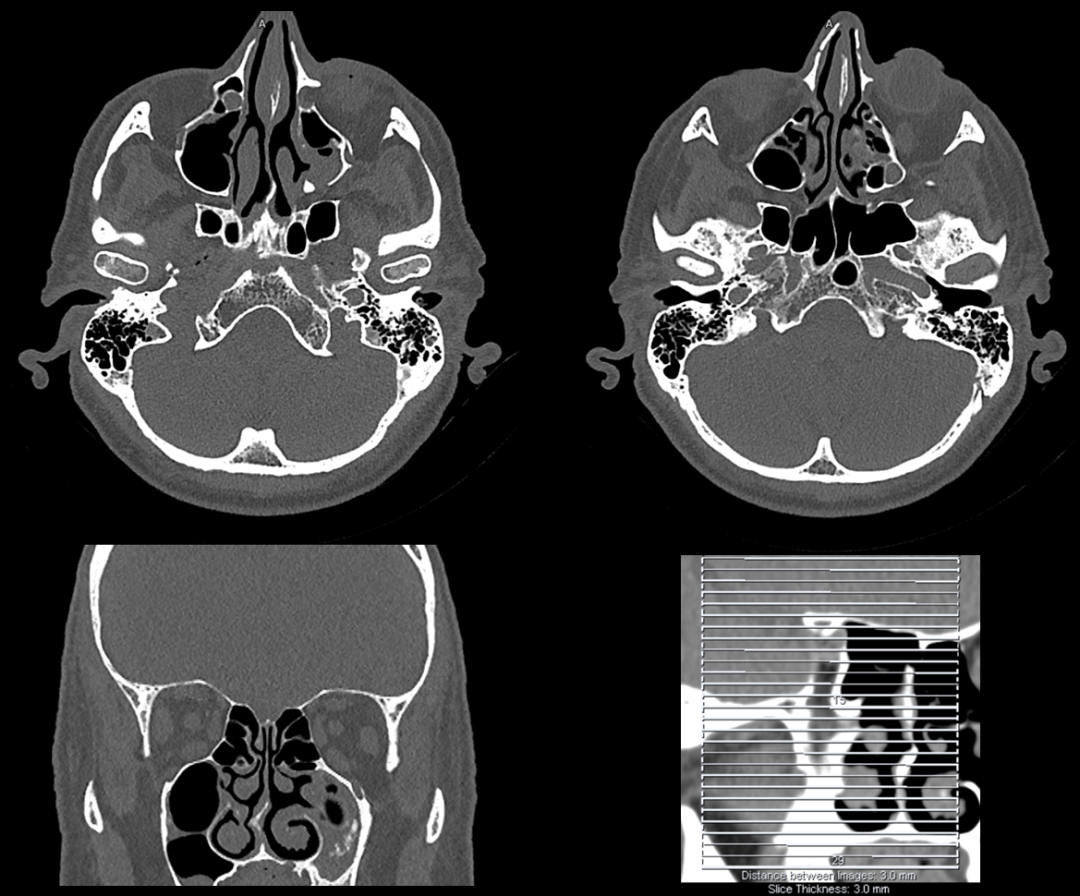

【一次扫描只需3秒,超高清成像,大小病灶一览无余】

· 超高清图像质量,大小病灶一览无余;